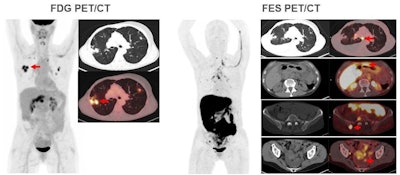

Images are from a 59-year-old woman with treated invasive lobular breast cancer and suspicion of disease recurrence. FDG-PET/CT showed FDG-avid lung opacities suspicious for lung cancer recurrence, but lung biopsy was benign. FES-PET/CT determined lung lesions were not FES-avid, but there were FES-avid nodal, gastrointestinal, osseous, and peritoneal lesions. Image courtesy of Dr. Gary Ulaner and SNMMI.Encouraging results